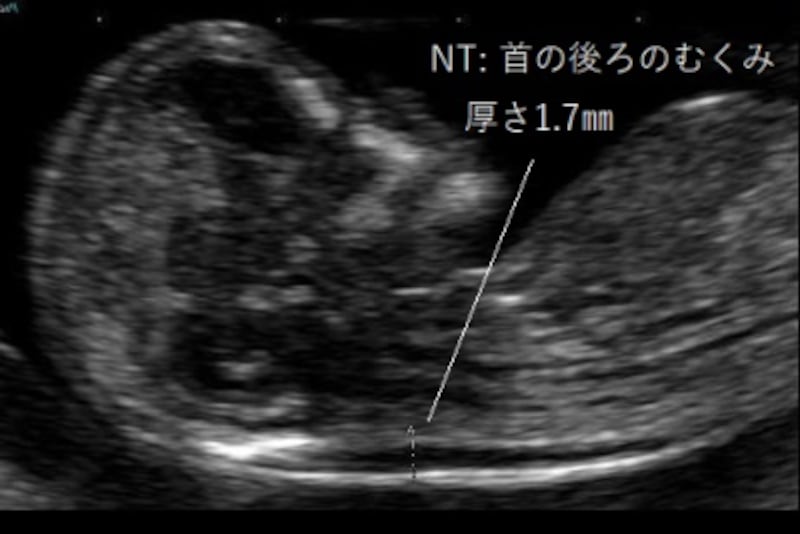

胎児の首の後ろのむくみ 浮腫 Nt とは 妊娠初期 All About

Nt Nuchal Translucency について 出生前検査 Nipt 遺伝カウンセリング 妊婦健診 エコー検査 産科 婦人科 産婦人科

胎児の首の後ろのむくみ 浮腫 Nt とは 妊娠初期 All About

胎児の首の後ろのむくみ 浮腫 Nt とは 妊娠初期 All About

胎児の首のむくみ Nt クリフム夫律子マタニティクリニック

02 妊娠初期 胎児の頸部浮腫 Nt 妊娠11 13週でcheck 深谷産婦人科 医学情報